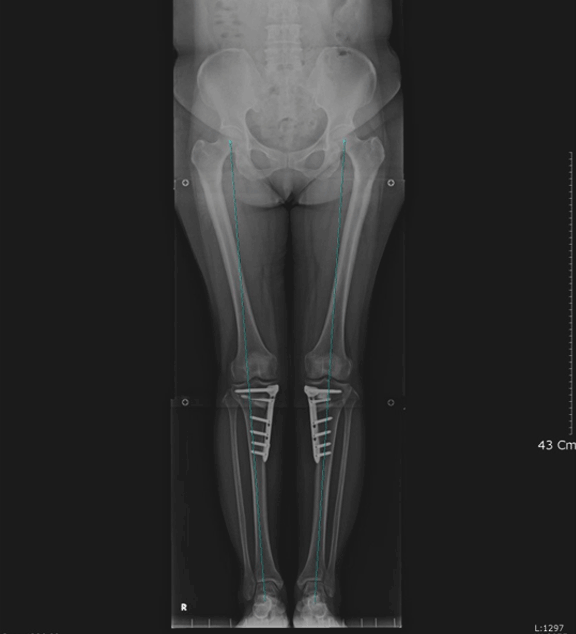

휜다리 교정술(근위경골 절골술)은 자기 관절을 보존하면서 통증 없이 일상생활을 영위할 수 있는 치료법입니다. O자로 휘어진 다리 변형은 무릎 내측 부위에 많은 스트레스를 주어 무릎 내측의 관절염을 빨리 진행시킵니다.

휜다리 교정술(근위경골 절골술)은 이런 무릎 내측 부위로 지나가는 몸의 무게 중심을 마모가 없는 무릎의 외측 부위로 옮겨 주어 통증 없이 보행 및 일상 생활을 할 수 있게 해주는 치료법입니다. 50대~60대 초반의 비교적 젊은 나이에서 무릎이 많이 휘어 관절염이 진행된 경우 시행하는 수술이며 주로 무릎 내측의 심한 통증으로 보행에 어려움을 호소 하는 경우 시행 합니다.

<다리가 안쪽으로 휘어진 O자 변형 다리>

<수술 후 다리 모양이 교정된 상태>